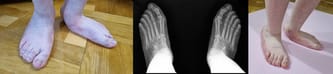

Stopy Ady są i zawsze były płasko-koślawe. Dotąd dobrze dobrane ortezy i odpowiednio prowadzona rehabilitacja pozwalały uniknąć operacji. Niestety, teraz stopień deformacji stóp jest tak duży, że utrudnia córce poruszanie się nawet w zaopatrzeniu ortopedycznym, sprawia ogromny ból. Tworzą się odciski. Chód bez ortez jest niemożliwy. Wada stale się pogłębia. Dziś stopy Ady są tak płasko-koślawe, że nie możemy już dobrać jej odpowiednich ortez. Aby ratować stopy córki, potrzebna jest kosztowna operacja. Tylko ona może uratować funkcję samodzielnego chodzenia.

Lekarze z Paley European Institute to godni zaufania specjaliści, w ręce których oddamy naszą córkę. Wszczepią Adzie specjalne implanty w stopy i nowatorską metodą uwolnią napięcie ścięgna Achillesa, aby nie spowodować utraty siły mięśniowej m.in. podudzia. Planowane leczenie poprawi jakość chodu córki, zapobiegnie dalszej deformacji stóp i stawów skokowych. Po operacji konieczne jest założenie opatrunków gipsowych poniżej stawu kolanowego na czas 4-6 tygodni. Kolejny raz Ada zostanie unieruchomiona, później czeka ją długa rehabilitacja.